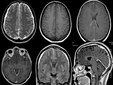

Beyin İçin Faydalı Besinler Beyin sağlığı, genel sağlık ve yaşam kalitesi açısından son derece önemli bir konudur. Günümüzde beslenme alışkanlıklarının beyin üzerindeki etkileri üzerine yapılan araştırmalar, belirli gıda maddelerinin beyin fonksiyonları üzerinde olumlu etkiler yarattığını göstermektedir. Bu makalede, beyin sağlığına katkıda bulunan besinlerin neler olduğunu ve bu besinlerin nasıl fayda sağladığını inceleyeceğiz. Omega-3 Yağ Asitleri Omega-3 yağ asitleri, beyinde yüksek oranda bulunan ve sinir hücrelerinin sağlıklı bir şekilde çalışmasını destekleyen temel yağlardır. Bu yağ asitleri, özellikle DHA (Dokosaheksaenoik Asit) ve EPA (Eikosapentaenoik Asit) açısından zengindir. Omega-3 yağ asitleri, aşağıdaki besinlerde bulunur: